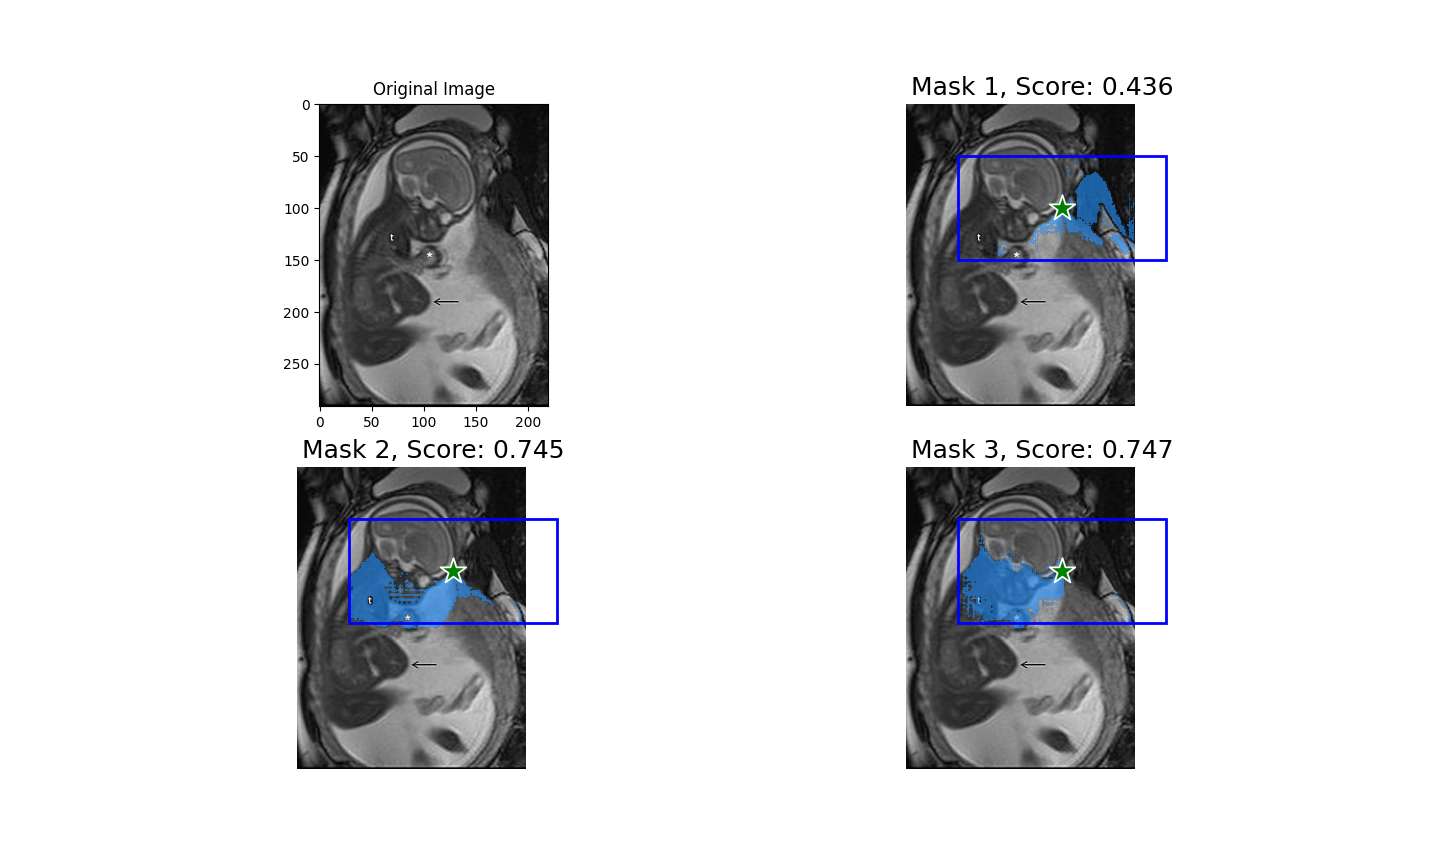

Ultralytics

Roboflow

OpenCV

My Portfolio

Some of the projects I've worked on.